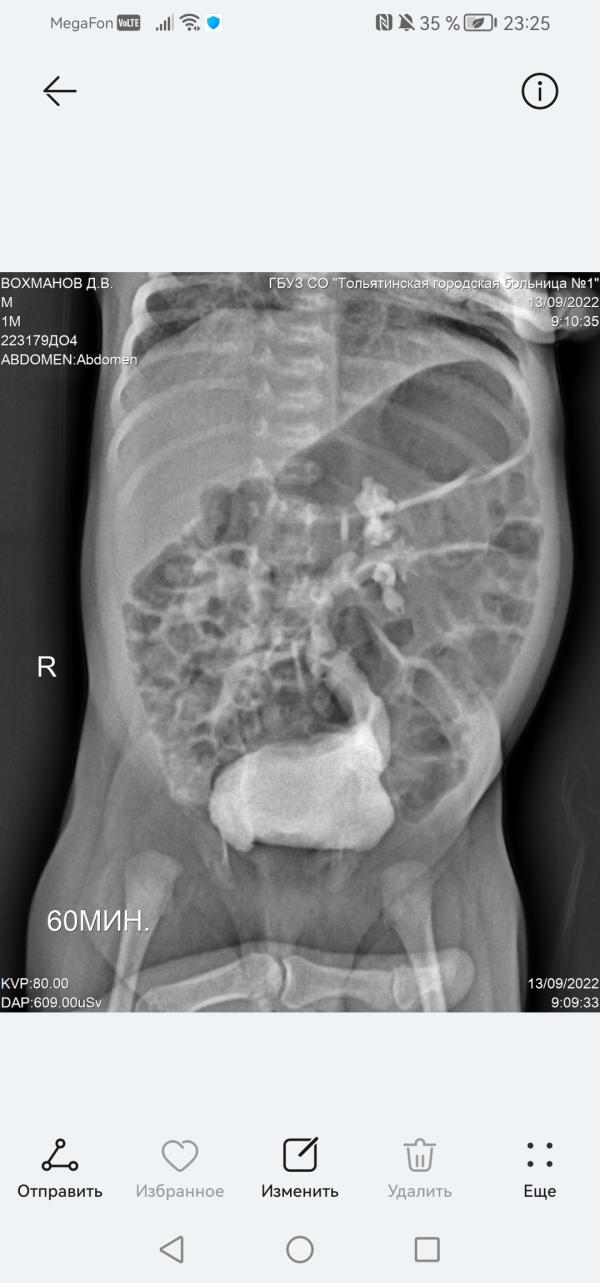

Сегодня мы ездили с Димой в Самару на консультацию к лучшему урологу нашей области Терёхину Сергею Сергеевичу.

Я такого врача ни разу в жизни не встречала. Добрый, отзывчивый, открытый человек, который максимально всё объясняет.

Диагноз гидронефроз нам снял. Есть расширение мочеточника на левой почки. Но оно может с возрастом пройти само. Контроль через 3 месяца. Узи.

Лейкоциты в моче в нашем случае связаны с застоем мочи. Что сдавать оам имеет смысл только в случае температуры. Что пичкать ...